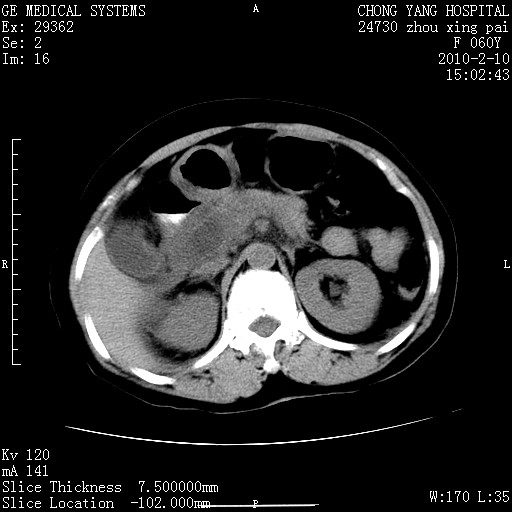

标题: CT24682:F60Y 腹痛 其它不详 [打印本页]

标题: CT24682:F60Y 腹痛 其它不详

胆总管末端梗阻!结石?胰腺影增粗,以胰腺头部为著,胰周看见渗出影,双侧胸腔积液,(胸膜反应)考虑胰腺炎。

1)胆总管末端梗阻,不排除结石所致可能。2)胰腺炎。3)慢性胆囊炎可能。4)左侧输尿管上段扩张。5)少量腹水。6)双侧少量胸腔积液,伴两下肺部分肺萎陷。

1)胆囊炎。2)胆源性胰腺炎。3)右肾周筋膜增厚,肾旁前间隙积液。4)左侧输尿管上段扩张。5)少量腹水。6)双侧少量胸腔积液,伴两下肺部分肺膨胀不全。

急性胰腺炎所致胆总管扩张!

1)胆总管末端梗阻。2)胰腺炎。3)慢性胆囊炎可能。4)左侧输尿管上段扩张。5)少量腹水。6)双侧少量胸腔积液,伴两下肺部分肺萎陷。